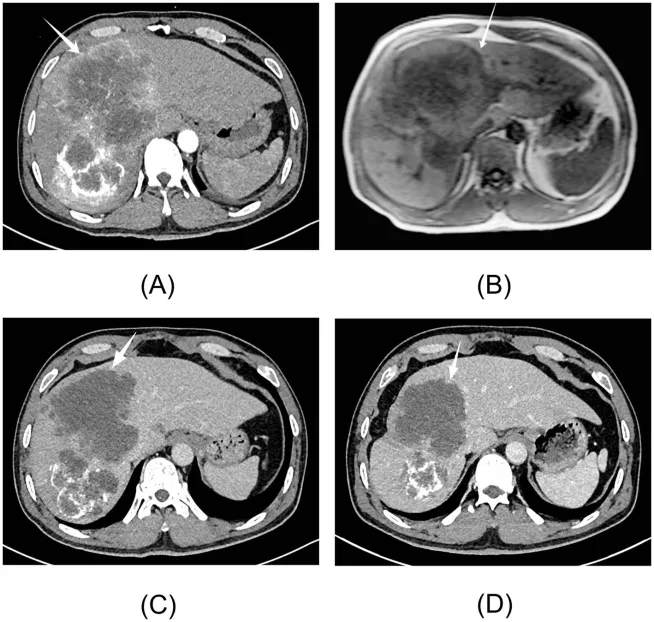

图3. 病例2的影像学表现

(A)初诊时腹部增强CT显示肝内巨大占位,最大截面约18.1×13.1 cm。(B)初诊时肝脏MRI(平扫及肝细胞特异性增强)提示肝内病变,最大截面约11.8×13.5 cm。(C)首次经导管动脉化疗栓塞术(TACE)后,肿瘤最大截面缩小至10.8×9.6 cm。(D)第三次TACE后,肿瘤进一步缩小至8.3×8.1 cm。

2025年2月确诊HCC后,患者立即接受TACE作为主要治疗,手术过程顺利,无急性并发症。术后规律服药,无特殊不适。2025年3月随访CT提示肿瘤缩小至10.8×9.6 cm,病灶仍呈不均匀动脉期强化(图3C);血清AKR1B10水平因肿瘤坏死释放反应性升高至3799.12 pg/mL,AFP持续阴性(3.25 ng/mL),遂行第二次TACE。

2025年4月复查显示肿瘤进一步缩小至9.3×8.4 cm,血清AKR1B10降至776.22 pg/mL,提示治疗有效,续行第三次TACE。2025年7月随访见主瘤缩小至8.3×8.1 cm,碘油沉积增加(图3D),AFP仍阴性(2.38 ng/mL),接受第四次TACE。

2025年9月复查显示肿瘤大小为7.8×7.6 cm,血清AKR1B10降至541.00 pg/mL,AFP持续阴性(2.95 ng/mL)。但患者出现肝病面容、皮肤巩膜黄染、肝掌等肝功能失代偿征象,本次未再行TACE治疗。图4动态展示了肿瘤影像与血清AKR1B10水平的时序变化。在整个治疗过程中,血清AFP水平始终维持阴性。